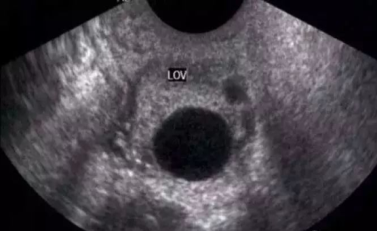

测量卵泡时显示卵泡最大切面后测量卵泡的长径和与之垂直的横径,取其平均值。在自然周期中通常只有一个卵泡发育成熟,其余的相继闭锁。当卵泡直径达10 mm时成为优势卵泡,自然周期中一般仅有一侧卵巢内有优势卵泡存在。优势卵泡的生长速度约为 1~2 mm/ d,近排卵前的卵泡生长速度可达 2~3 mm/d,当卵泡直径达18~20 mm时成为成熟卵泡,呈椭圆形或圆形,内为无回声区,边界清楚,有一定张力,常突于卵巢表面。